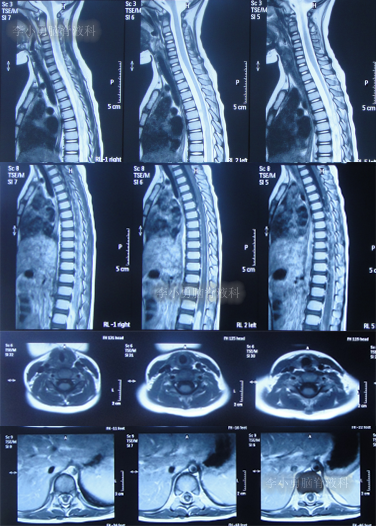

住院治疗7天即2022年5月18日,出现头痛,呕吐,体温再次升高为39.6度,心电图示室性心动过速,室早,考虑“心肌炎”,查头颅核磁(图-1)后并行腰穿见脑脊液呈金黄色,留取脑脊液送常规化验提示诊断为颅内感染,给予抗感染治疗。

图-1:2022年5月18日头颅核磁